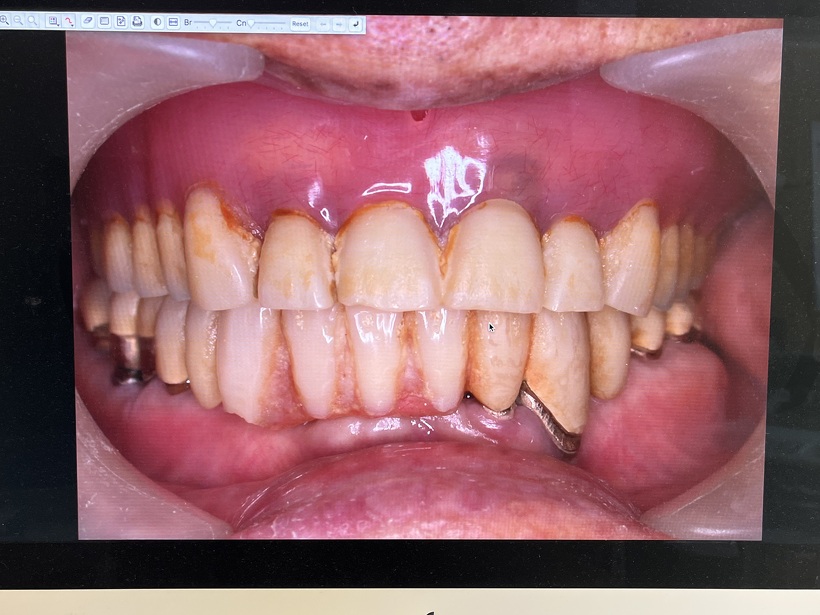

治療の結果上下で10本が残りました。上顎は2本の歯を総義歯の中に組み込みました。下顎のコーヌスブリッジ義歯 8本の支台歯(実際は7本ですが右下6番は根を2つに分割して使用しています)で14本の歯を作りました。

80歳から96歳まで16年間拝見しました。16年間で失った歯は亡くなる直前に0.5本でした。歯周病・糖尿病・癌の状態もよく最後は自宅で亡くなりました。歯周病と糖尿病と癌はお友達疾患であり、歯周病の状態が改善すれば悪い友達も寄り付かなくなります。